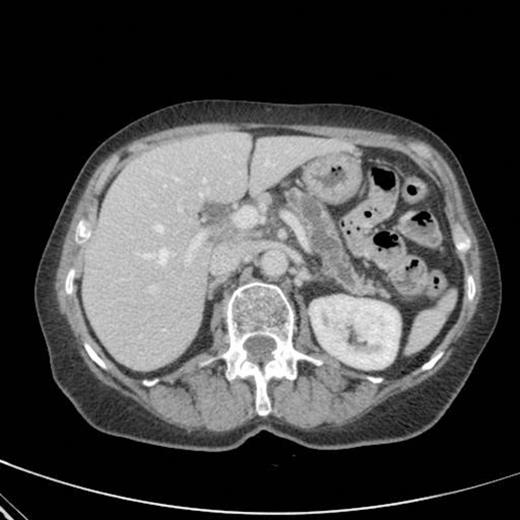

CT scan done at 10 years after initial diagnosis as part of routine surveillance revealed gross dilatation of main pancreatic duct to 10 mm along with a widely patent communication between the pancreatic duct and the stomach raising the possibility of a spontaneous gastro-pancreatic fistula measuring up to 19 mm associated with layering of mucin within the stomach. (Fig 3). The pancreas did not reveal any mass lesion and was globally atrophic. An upper GI endsocopy was done and this revealed a little crater with mucus plug in the body of the stomach along the lesser curve representing the opening of the gastropancreatic fistula. Biopsies taken around the fistula revealed non-specific inflammation. On clinic review, the patient complained of increased frequency of bowel habits, which was thought to be due to intestinal hurry caused by the fistula. This responded well to increased dose of creon.